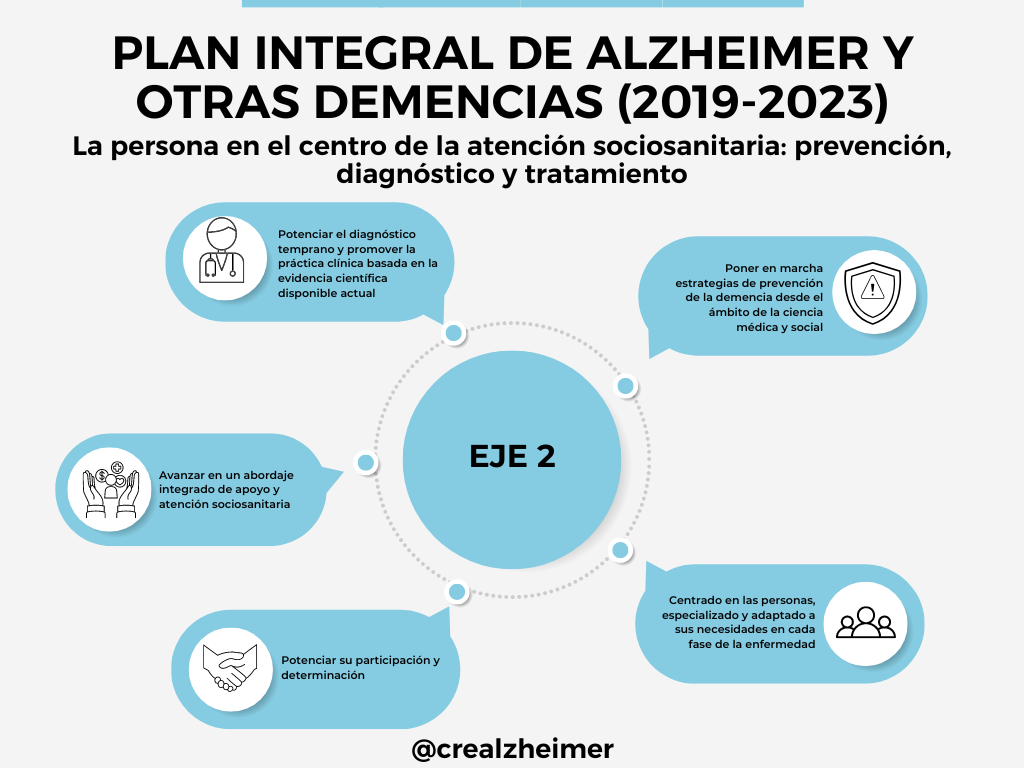

Eje 2: La persona en el centro de la atención sociosanitaria: Prevención, diagnóstico y tratamiento

Información relacionada con el Plan Integral de Alzhéimer y otras demencias (2019-2023)

INFOGRAFÍA